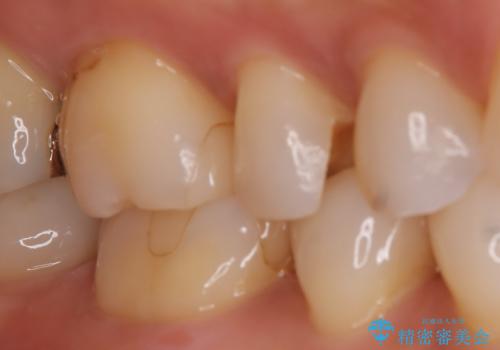

【セラミックインレー】昔治療した詰め物が外れた。

- 他院でいれたセラミックインレーが脱離して、来院されました。

新たに製作を希望されたため、当院で治療しました。